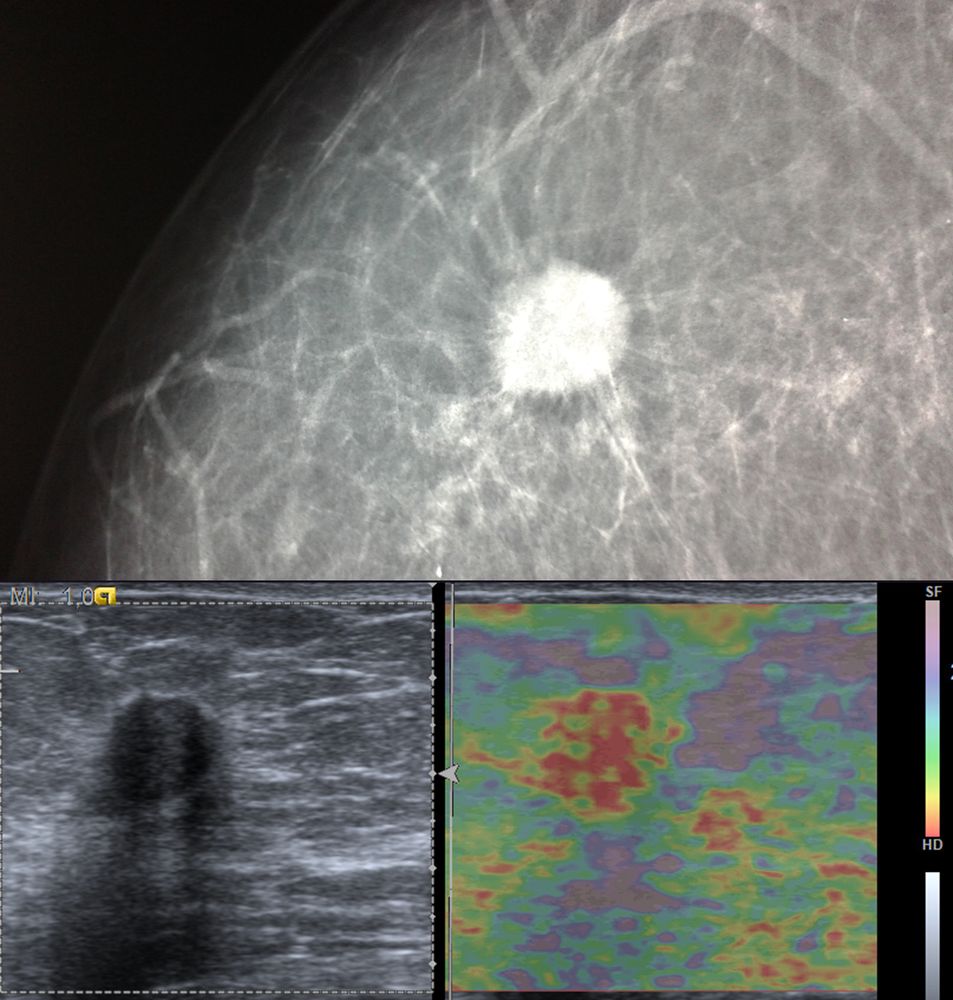

Η ελαστογραφία μαστού είναι μια σύγχρονη υπερηχογραφική μέθοδος που επιτρέπει τη διάκρισητων καλοήθων ογκιδίων από τους κακοήθεις όγκους.

Συνοπτικά ασκείται μια μικρή πίεση στους εντοπισμένους όγκους, μετρώντας την ελαστικότητα τους.

Ο καρκίνος γενικά εμφανίζει μεγαλύτερη σκληρότητα-ελαττωμένη ελαστικότητα σε σχέση με τα καλοήθη ογκίδια και επομένως η ελαστογραφία μπορεί να δώσει τις αναγκαίες πληροφορίες έτσι ώστε να μειώσει τις βιοψίες μαστού μόνο στις απολύτως απαραίτητες.